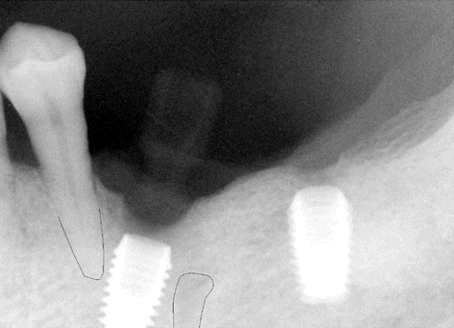

Fig.1 38 year-old male patient presented in 2006 with chief complaint "loose bridges". Exam shows poor oral hygiene and restoration, and advanced periodontal disease. Initial treatment includes removal of grossly nonsalvageables, scaling & root planing, and upper removable partial using #1 as distal abutment. Due to pneumatic sinuses and finance, implants would be placed in the mandible first. | |

Fig.2 High looped mental nerve is noted pre-op. To avoid potential damage to the nerve, local infiltration was used. Flap was raised to expose the mental nerve before osteotomy. A shorter implant was chosen for #29 (5x6mm), as compared to 5x8 implants (Bicon) for #28 and 30. The depth of osteotomy for #29 was controlled so as not to pass below the mental foramen, but still to bury implant platform. According to manufacture manual, the implant should be buried 2-3 mm below the ridge. No paresthesia was found post-op, although #29 implant was apparently on the top of the mental nerve (red tracing line). As shown below by cone-beam, the apex of this implant must be located lingual to the mental nerve when the latter exits the mental foramen. The drawback is that a few of threads was exposed buccally for #29 implant (not shown), probably because it was not buried deep enough. The thread exposure was found during uncovering, 4 months after placement. No further treatment was pursued for thread exposure. Integrated abutment crowns were placed for #28-30. This panorex was taken 1.5 years after crown placement. Radiographically, implant thread is below the alveolar ridge. Twenty eight months since functioning, these 3 implant-supported crowns have been stable with healthy bone and gingiva. | |